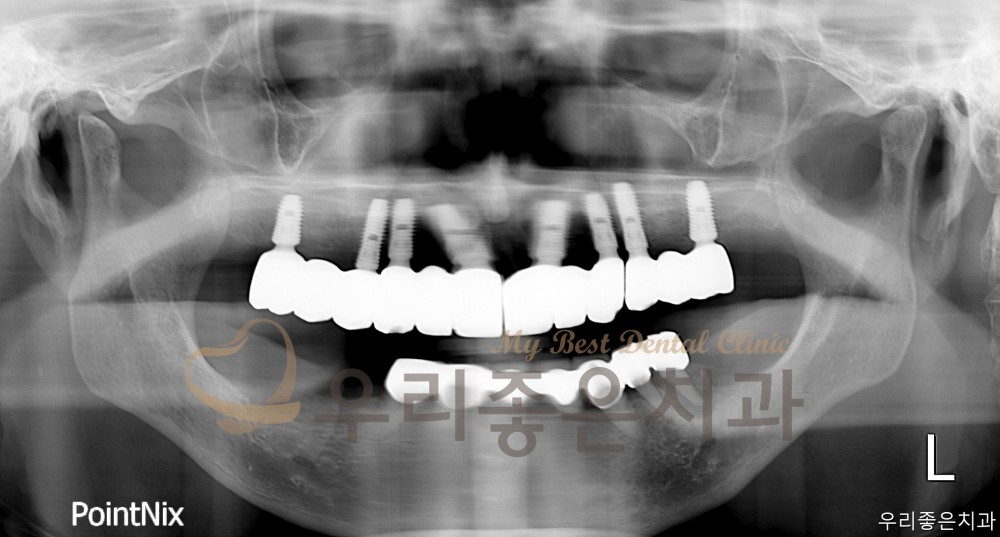

인쇄 목록 임플란트 | 우리좋은치과 상악 임플란트 풀케이스 (김** 25.03.25~25.08.13) 페이지 정보 우리좋은치과 549 0 2025-09-30 16:10:45 본문 BEFORE AFTER Before After Before After 우리좋은치과 상악 임플란트 풀케이스 인쇄 목록 이전글 ▲우리좋은치과 앞니 충치로 인한 레진 치료 (신** 25.10.02 당일치료) 다음글 ▼우리좋은치과 앞니 재보철 치료 (유 ** 25.09.23~25.09.30) 댓글목록 등록된 댓글이 없습니다. 이전글 다음글 목록